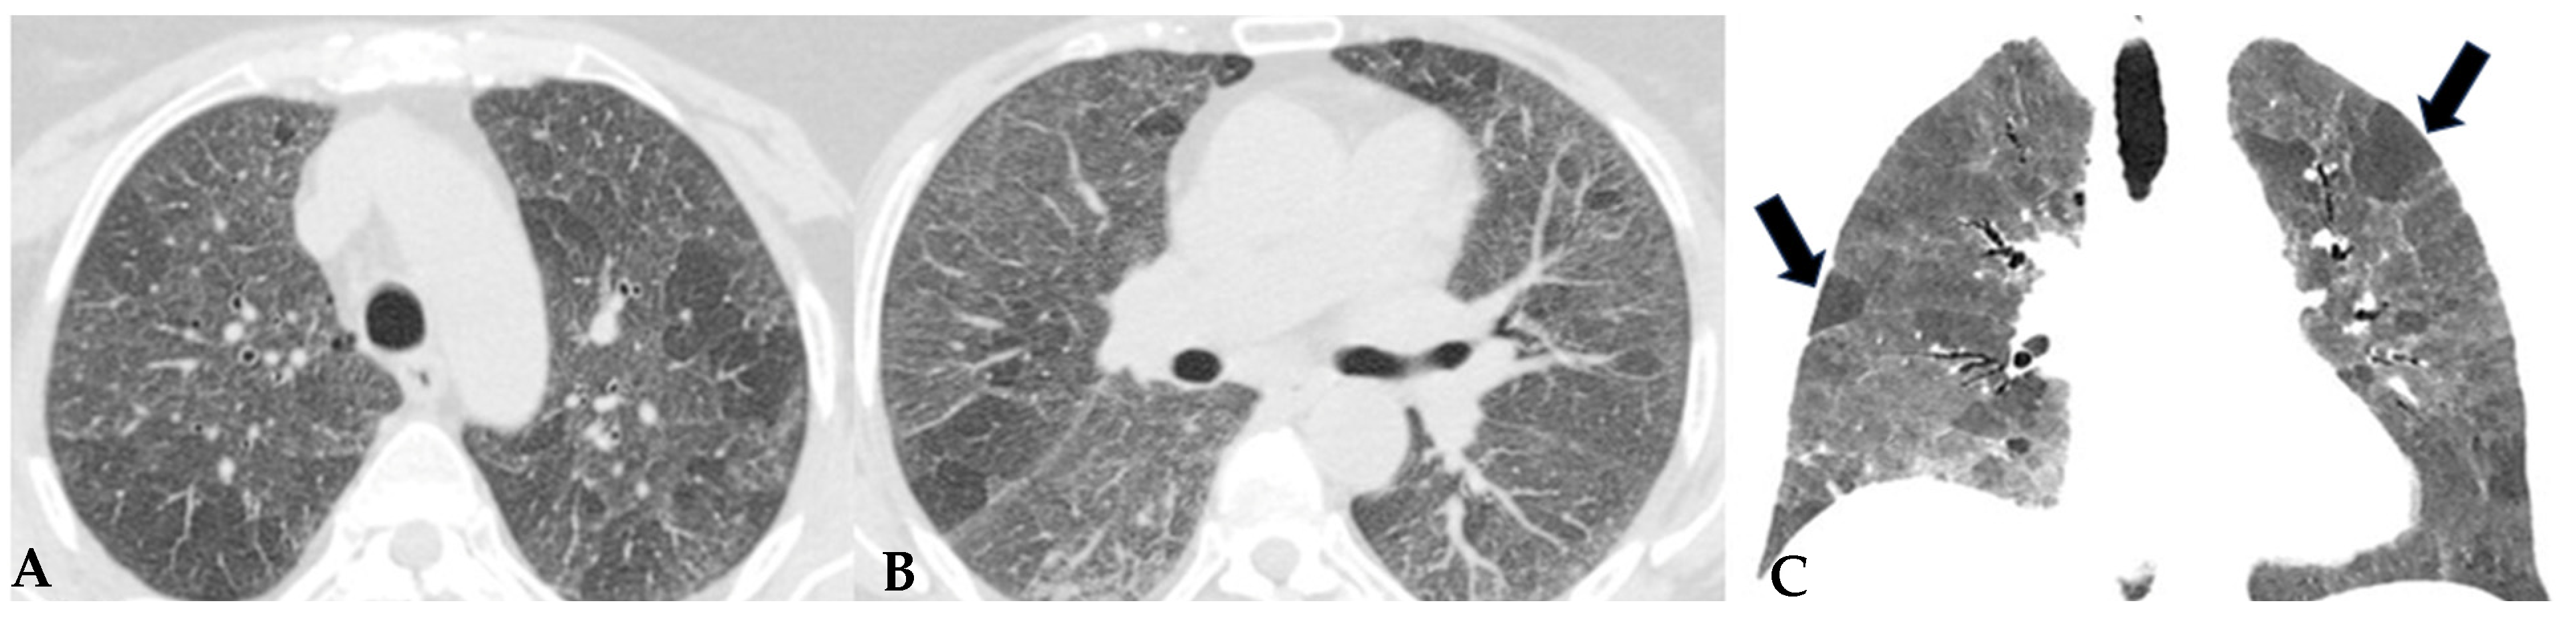

Figure 8.

Axial chest HRCT scan. Asymmetric fibrotic alterations with volume loss on the right in the upper lobe (A); in the lower lobes on the right, a significant extensive area of reduced attenuation is evident, suggestive of air trapping (red box), with components of distorted GGO and fibrosing characteristics with intra- and interlobular thickening and traction bronchiectasis/bronchiolectasis (B).

The absence of characteristic features of a “typical HP pattern” poses the “compatible with HP” pattern as a diagnostic challenge in distinguishing it from some other patterns, including NSIP and atypical forms of UIP/IPF. The clinical presentation can be insidious, characterized by an occasionally silent course, and likely correlated with the absence of a specific acute event of NFHP. Nevertheless, it exhibits non-specific clinical features analogous to other fibrotic ILDs, including dry cough and dyspnea, which may slowly lead to chronic respiratory failure like other idiopathic or secondary forms.